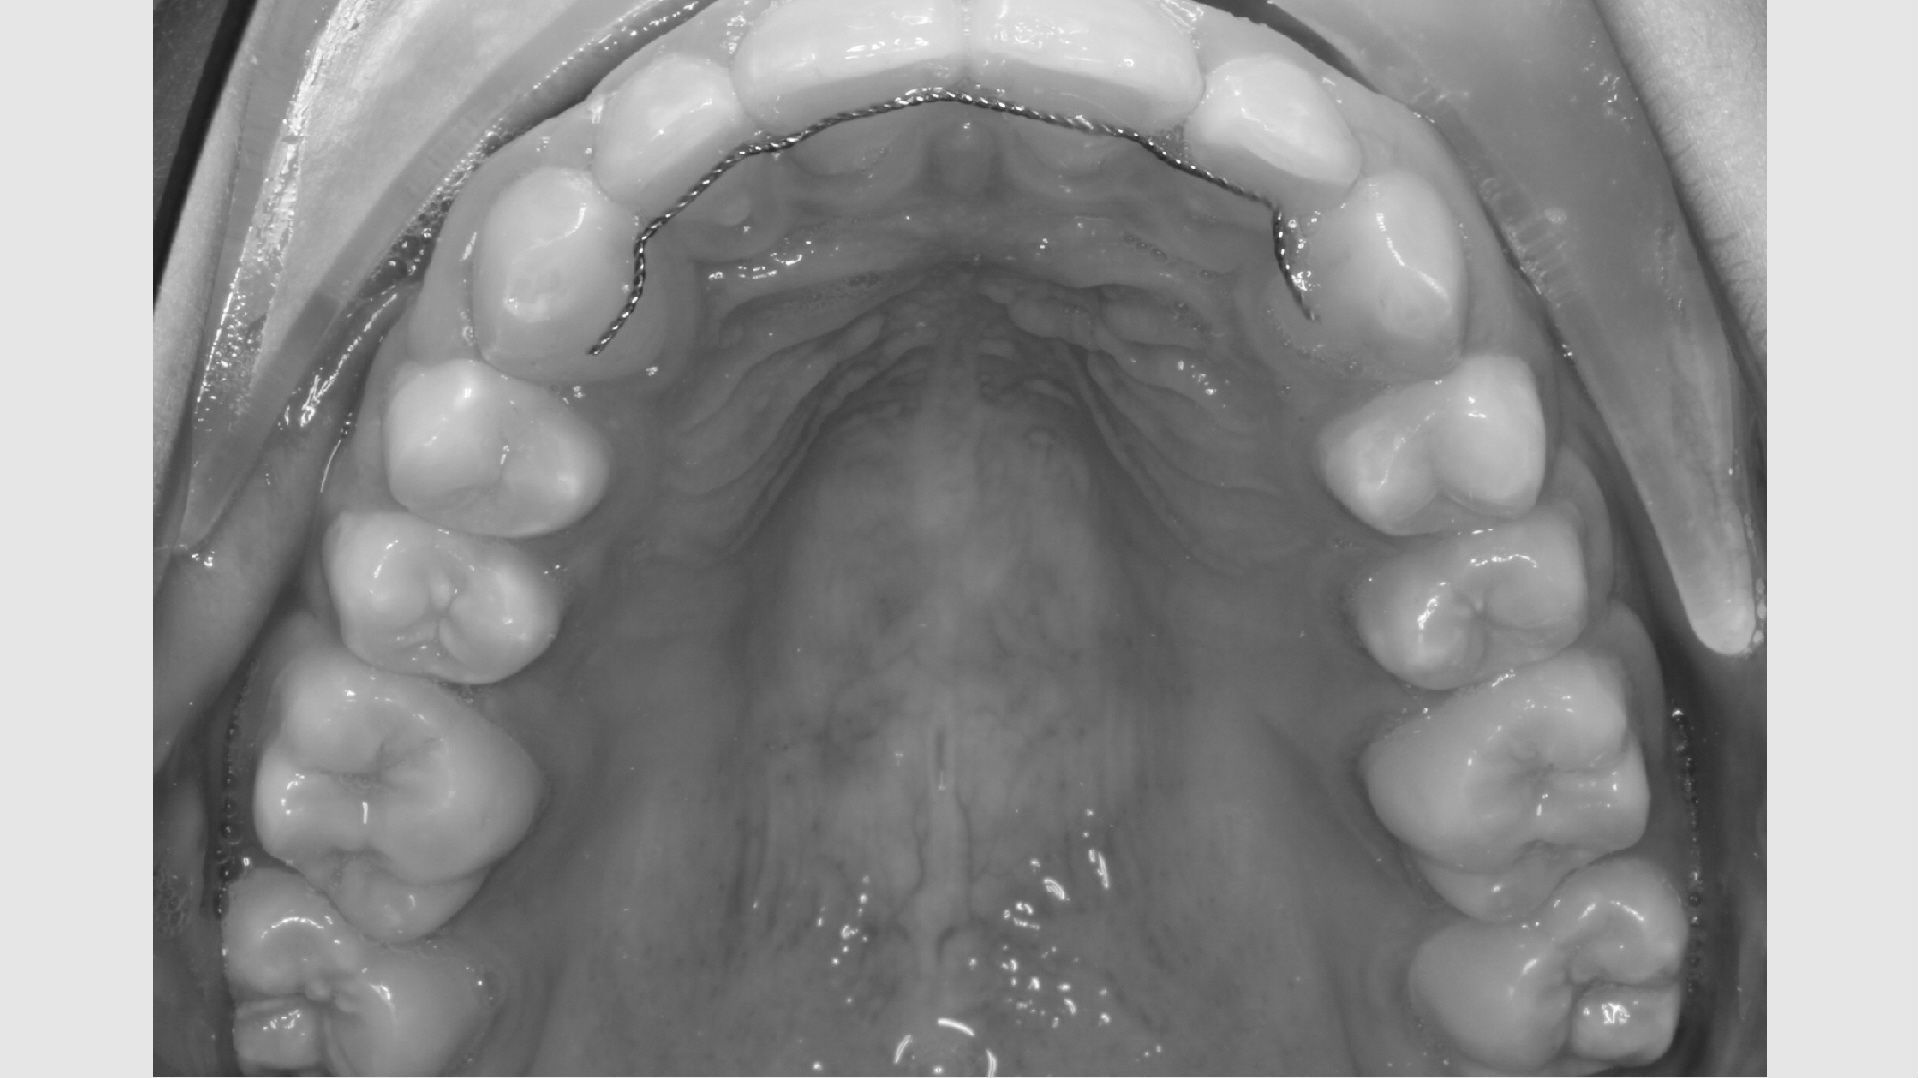

Første gang dit barn besøger Tandreguleringsklinikken, bliver der lavet studiemateriale.

Studiemateriale, består af modeller, fotos og røntgenbilleder af tænder og ansigt. Der bliver også udleveret et helbredsskema, som skal udfyldes på stedet. Det er vigtigt at vide, om jeres barn er sundt og raskt, eller om der er særlige hensyn, vi skal tage - eksempelvis til medicin med videre.

Der bliver taget billeder "udenpå og indeni" samt røntgenbilleder.

Dit barn skal selv holde sine læber til side med en læbeholder, mens tænderne bliver fotograferet. Billederne har følgende formål:

• Panorama viser, om alle tænder er anlagt, og om tandrødder og kæbeled ser normale ud.

• Profilrøntgen giver et billede af, hvordan kæberne er placeret i forhold til hinanden og i forhold til resten af kraniet. Derudover giver det et indtryk af, hvordan væksten vil udfolde sig.

• I nogle tilfælde tages der også et røntgenbillede af hånden, for at se hvor langt dit barn er i sin vækst.

• Der tages røntgenbillede af fortænderne i overkæben som et referencebillede, da disse af og til bliver skadet lidt af en bøjlebehandling. Cirka et halvt år inde i behandlingen bliver der taget ét billede igen som kontrol.

• Alt materiale studeres af en specialtandlæge, der udarbejder en behandlingsplan.